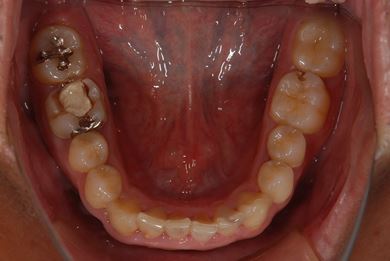

インプラントの症例写真 IMPLANT

抜歯即日スピードインプラント治療

| 性別/年齢 | 男性 / 38歳 | ||||||||||||||||||||||||||||||||

| 主訴 | 10年位前に虫歯治療をした右下奥歯のつめ物が取れ、再治療を受けた際にインプラントをすすめられたため、治療相談で来院。 | ||||||||||||||||||||||||||||||||

| 治療方針 | 抜歯と同時にインプラントを埋入し、治療期間を短縮する。 | ||||||||||||||||||||||||||||||||

| 治療内容 | インプラント1本(抜歯即日スピードインプラント)、ハイブリッドセラミッククラウン1本 | ||||||||||||||||||||||||||||||||

| 総治療費 | 257,250円 | ||||||||||||||||||||||||||||||||

| 治療期間 | 6ヶ月 |